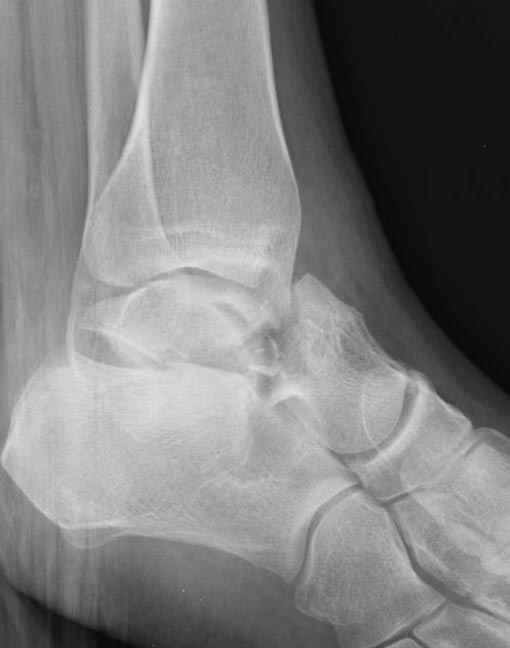

Уважаемые участники русского Ортофорума, поздравляю всех со всеми прошедшими праздниками: Новым годом, Рождеством, Hanukkah, Kwanzaa, желаю участникам всего наилучшего и здоровья.Повреждение таранной кости.Больной 81г автоавария, повреждение таранной кости, здесь снимки. Какие рекомендации?Djoldas Kuldjanov, MDDepartment of Orthopedic SurgerySt. Louis University Medical Center

Вдогонку по поводу перелома таранной кости, больная 81, не страдает диабетом, перелом закрытый, в первый же день поступления ограничились временным наружным фиксатором (как на снимке).

Планировалась открытая фиксация после спадения отека, но больная пожелала лечиться по месту жительству в другом штате..

Примеры на снимке...